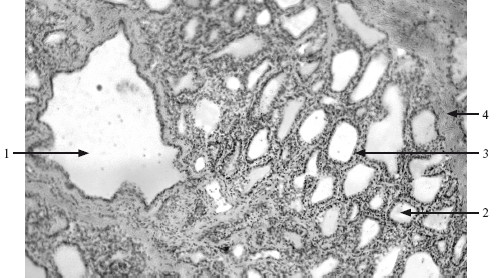

Функционально активная (лактирующая) железа образована дольками, состоящими из альвеол, между которыми располагаются внутридольковые протоки. Форма клеток в альвеолах варьирует в зависимости от степени растяжения и фазы секреции (рис. 16.2).

Рис. 16.2. Лактирующая молочная железа. х 132.

1 – млечный ход; 2 – концевой отдел; 3 – экзокриноциты; 4 – соединительно-тканная перегородка.